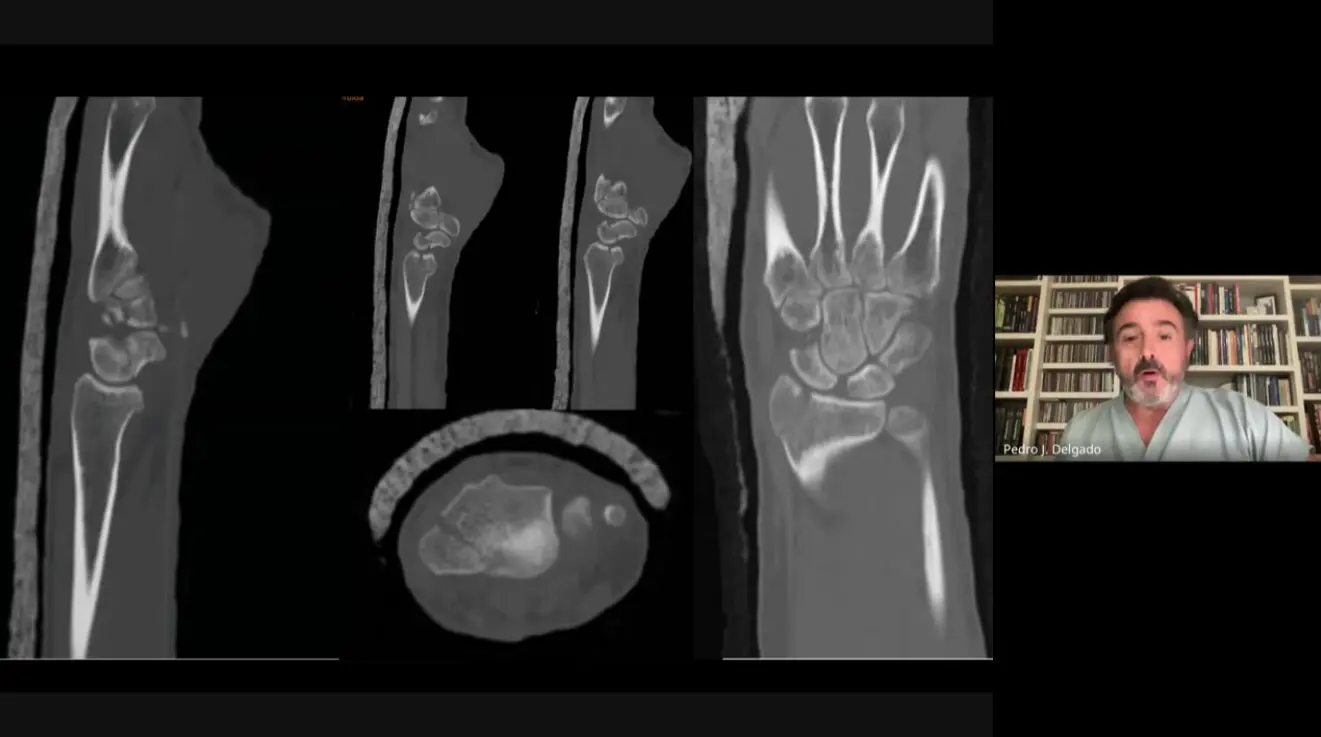

Abordaje de Fracturas Intraarticulares Complejas: Se presentó un caso de un paciente joven con una fractura intraarticular compleja de radio distal y afectación del escafoides. Pedro J. Delgado la consideró quirúrgica, especialmente por la afectación del escafoides y la inestabilidad de la fractura, que involucra gran parte de la articulación radial y se asocia a lesiones ligamentosas. Su secuencia preferida incluye primero una artroscopia para visualización, limpieza del hematoma, y prueba de reducción, para luego proceder con el abordaje palmar.

Uso de Clasificaciones en Fracturas de Radio: Pedro J. Delgado indicó que en su equipo no son partidarios de las clasificaciones de fracturas, ya que, aunque útiles para estudios y registros, no indican el tratamiento a seguir ni las lesiones asociadas. Él y su equipo se basan más en los datos del paciente (diestro, dominante, trabajador, deportista) y en la radiografía post-reducción, además de la tomografía computarizada (TAC) para identificar fragmentos clave.

Avances en el Tratamiento de Fracturas de Radio Distal: Se discutió qué ha revolucionado el tratamiento de fracturas de radio distal en los últimos 10 años. Pedro J. Delgado destacó la fácil disponibilidad del TAC, la capacidad de usar el artroscopio sin restricciones, y la mejora en las placas, especialmente las preformadas, que han simplificado gestos quirúrgicos. Vicente Carratalá añadió la poliaxialidad de los tornillos, que permite posicionarlos donde es más necesario.